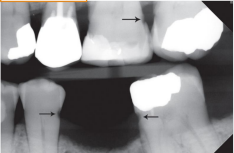

top arrow, classify this lesion based on the ADA caries classification system

D1

bottom arrow, classify this lesion based on the ADA caries classification system

D2